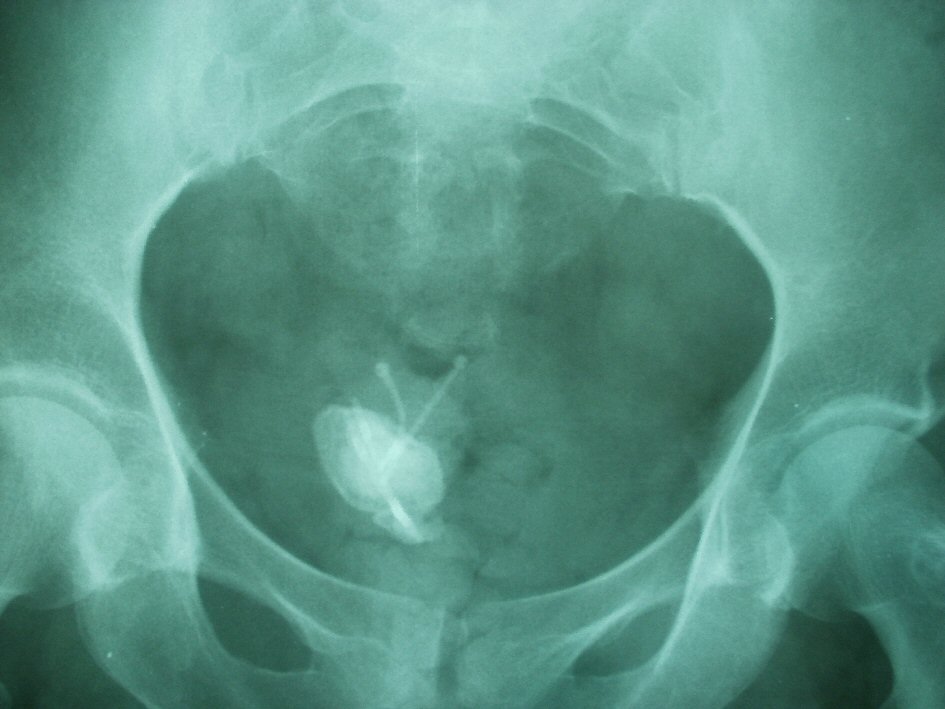

The patient’s medical history indicated that a copper-T IUCD had been inserted in 1999, 3 months following her third normal vaginal delivery. She had unexpectedly conceived again 4 years after insertion and had a normal vaginal delivery without any complication. It was assumed that the IUCD had fallen out and another copper-T IUCD was inserted 3 years after her fourth delivery. As per records both devices were placed correctly in the uterus and the procedures were uncomplicated. Hysterectomy was done in 2011 and it was also assumed that the second IUCD was removed with hysterectomy. Pelvic examination was normal. A plain abdominal radiograph showed the presence in the pelvis of a large stone opacity with dimensions of 3.9 × 3.4 cm around the horizontal limbs of both double IUCDs (Fig. 1) which was confirmed by pelvic ultrasonography. Cystoscopy confirmed the presence of two intravesical IUCDs, complicated by stone which was fragmented endoscopically using stone crushing forceps. Both fragmented calculus and IUCDs were removed cystoscopically by grasping forceps (Fig. 2). The patient was discharged 1 day after removing the IUCDs, with uneventful evolution.

![]() Click for large image | Figure 1. X-ray of the pelvis demonstrates two intrauterine contraceptive devices (IUCDs) within the pelvic cavity with calculus formation on the horizontal limb of both IUCDs. |